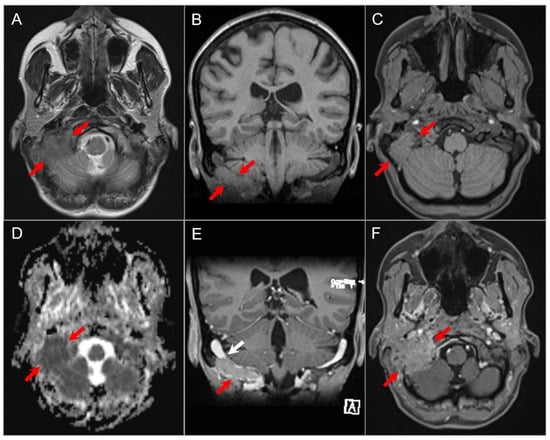

4.1.2. Schwannoma

4.4.1. Chordoma

4.4.2. Chondrosarcoma